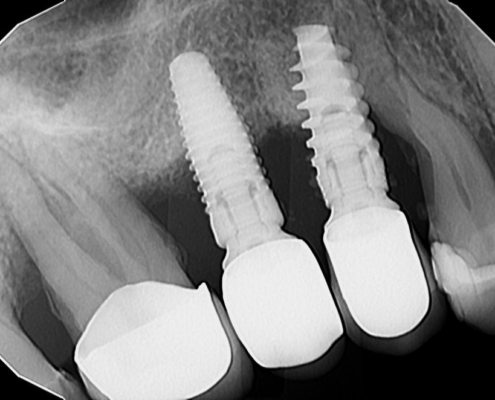

Periimplantitis je upalno patološko stanje koje zahvaća tkiva u neposrednoj okolini dentalnog implantata, pri čemu dolazi do upale periimplantatne sluznice i postupnog gubitka koštanog potpornog tkiva. Kliničke manifestacije periimplantitisa uključuju upalu, krvarenje pri sondiranju, supuraciju, povećanu dubinu sondiranja i gubitak kosti (Slika 1.). Upala mekih tkiva obično se otkriva krvarenjem pri sondiranju, dok se gubitak kosti prepoznaje na radiografskim snimkama kao ˝krater˝ oko implantata uz povećane dubine sondiranja (Slika 2.). Dubina sondiranja može ukazivati na ozbiljnost bolesti i korelira s gubitkom kosti, čija brzina varira među pacijentima (1). Periimplantitis se često razvija kod pacijenata s prethodnom anamnezom uznapredovalog parodontitisa, lošom kontrolom plaka te nedostatkom redovite terapije održavanja nakon implantološkog zahvata.